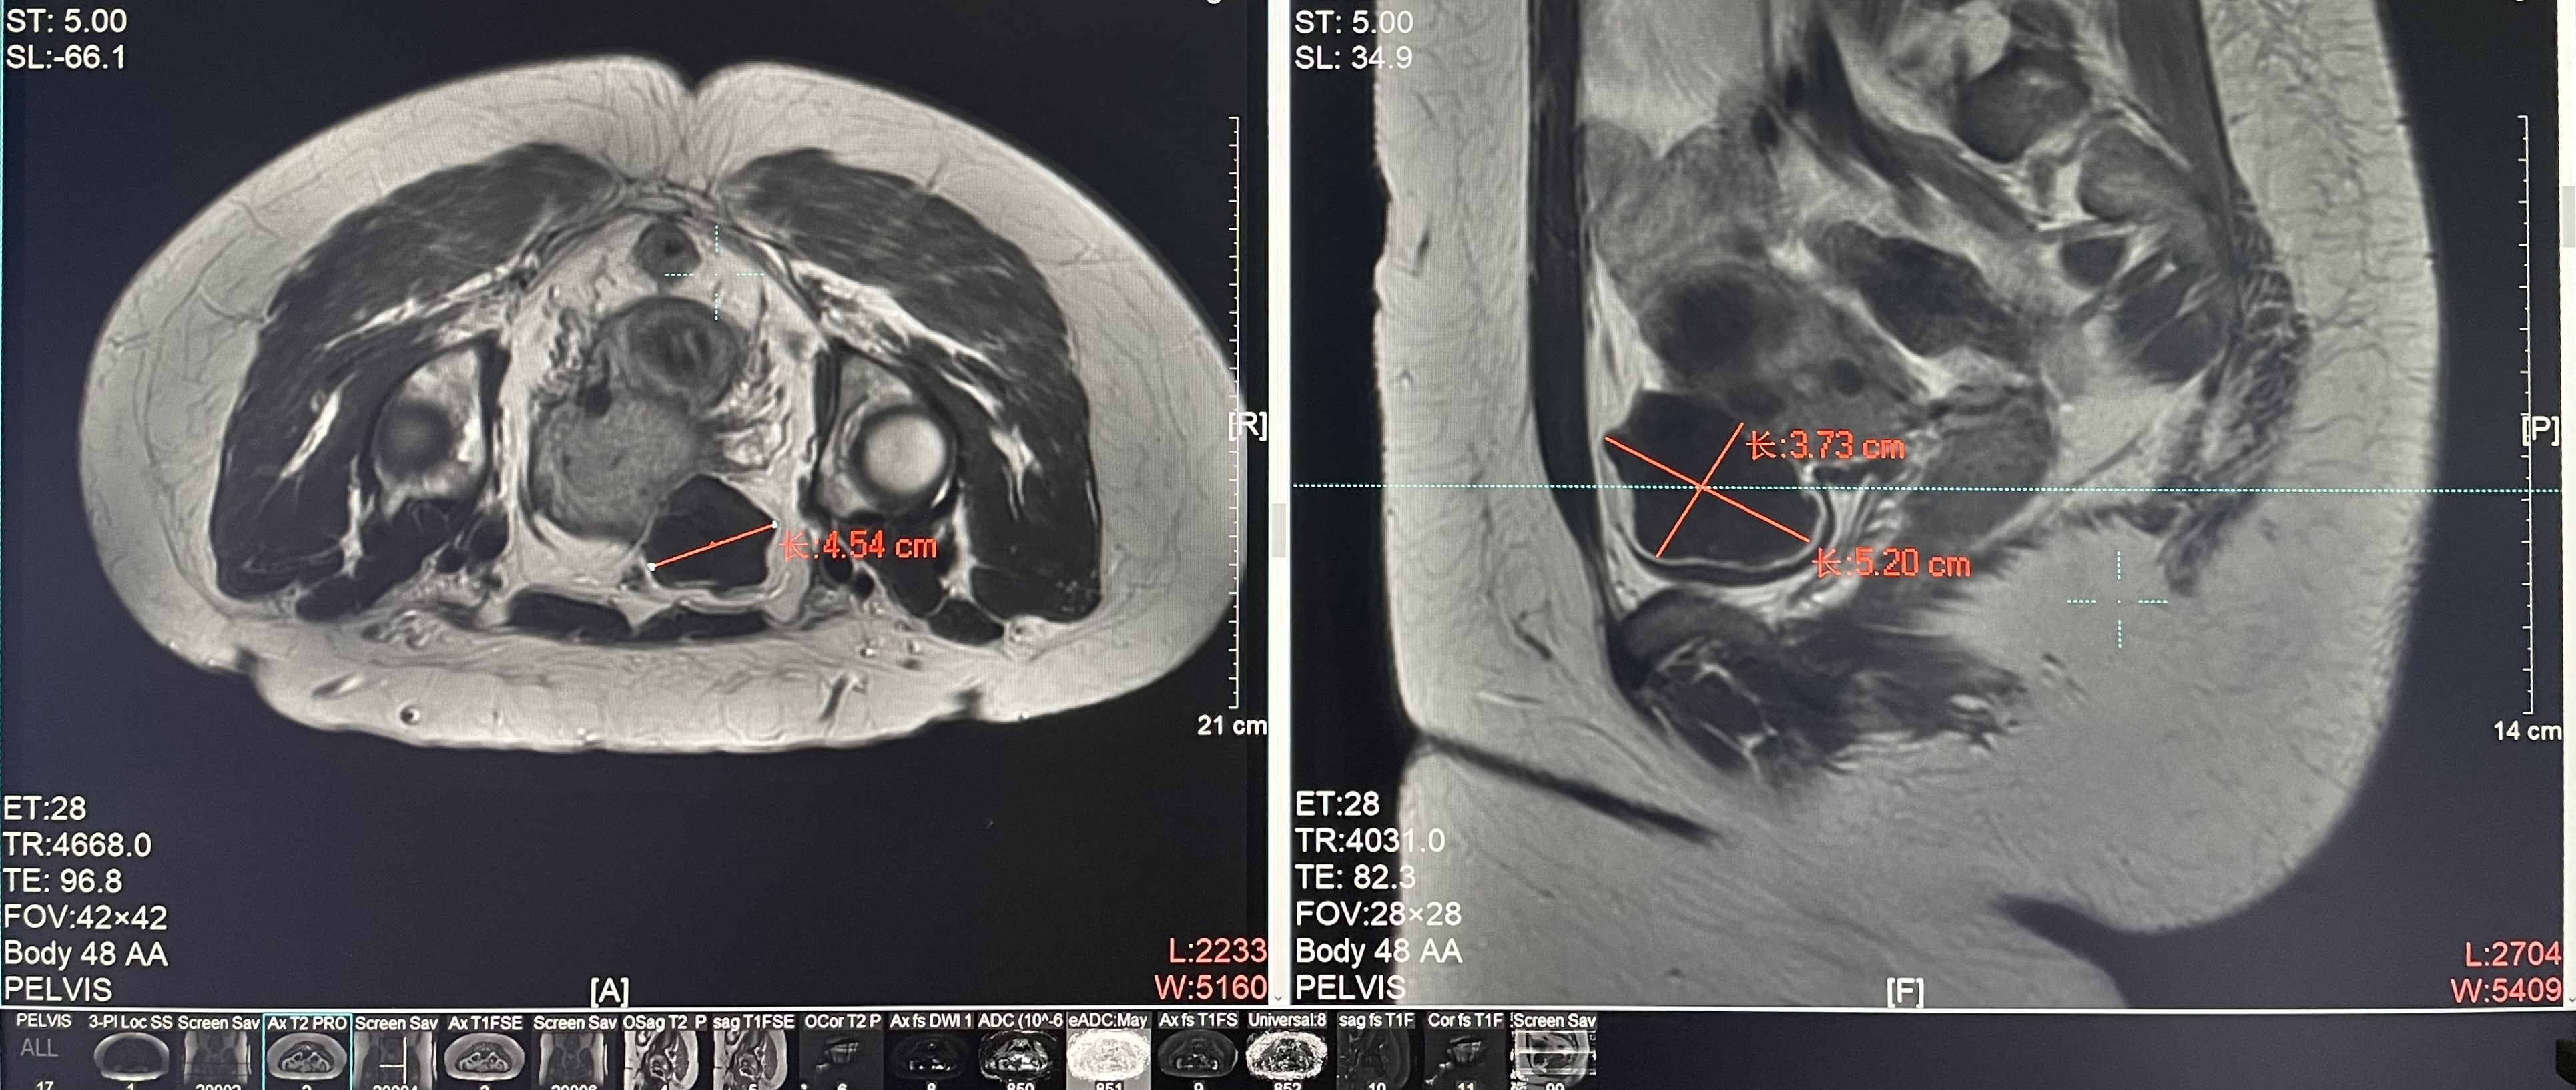

Uterine fibroids

Patient Information:Female,38

Diagnosis: Uterine fibroids

Tumor size: about 45*52*38mm

ROT depth: The ROT center of the tumor is mm from the skin

Postoperative evaluation: Postoperative enhanced imaging showed a good overlap between the ablation area (right) and the tumor area (left), the non-perfusion area was continuous and consistent.

Conclusion:It has a excellent ablation effect on this tumor, and the temperature rise curve during treatment is in line with expectations. The 240CEM area of each treated target is large, full and continuous.The ablation effect was very good,the NPV volume ratio was about 70%.